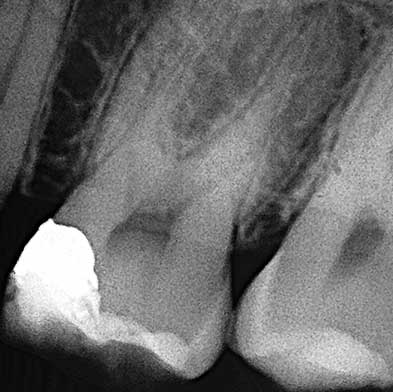

Endodoncia

Dra. Carmen Feito Bárcena